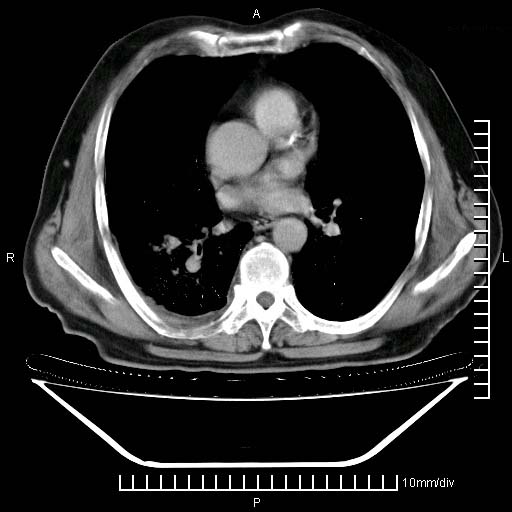

标题: CT24043:胸部增强:男性,60岁

既往肺结核,近10几天,咳嗽,咳痰,右侧胸痛,疼痛较明显,右上肺斑块考虑结核灶胸膜粘连,增强,可惜动脉期没有定好,未见强化,可延迟4分后又见较明显强化,中心见低密度影,如果说结核是边缘强化,可这个灶强化的面积挺大的,让人很挠头。

延迟4分后

[img][/img]